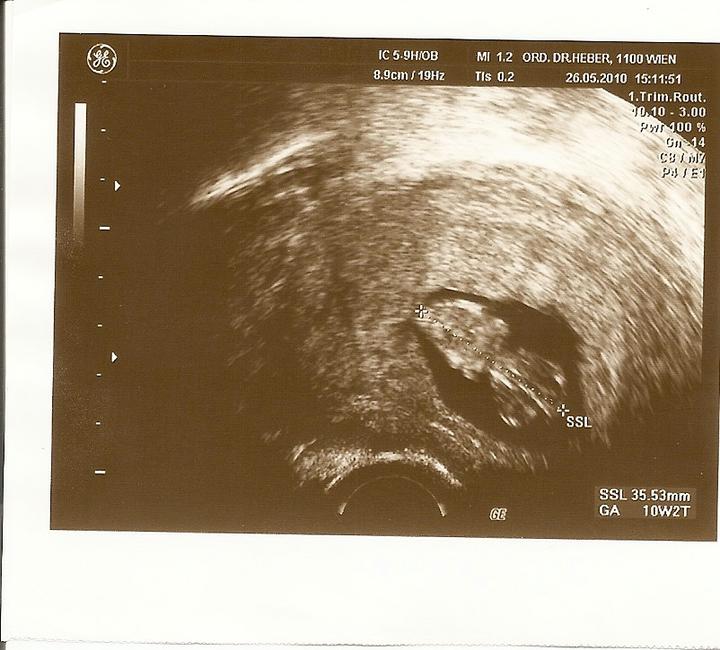

Za2tyzdne uvidim zase moje mimi na utz

Za17dni sa mozno dozvieme co mame v brusku